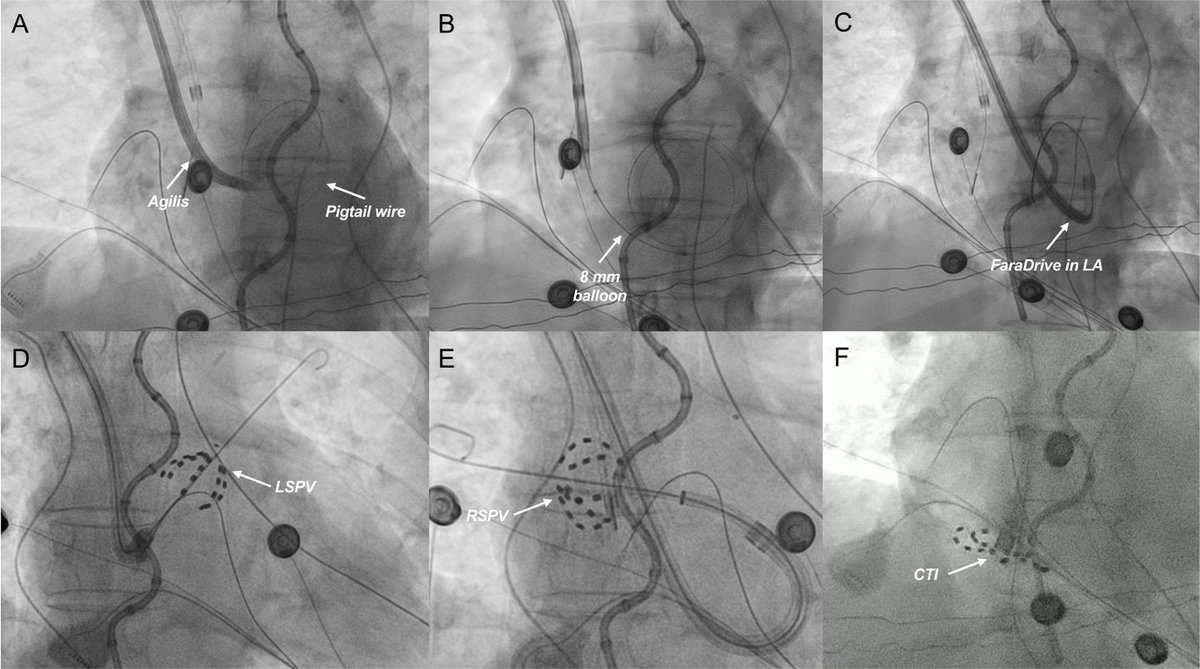

PVI With Pentaspline PFA From an Axillary Venous Approach in a Patient with Interrupted IVC: First US Report @CleClinicHVTI @tavrkapadia @BalintLaczay

https://t.co/AZEEa9iN4f